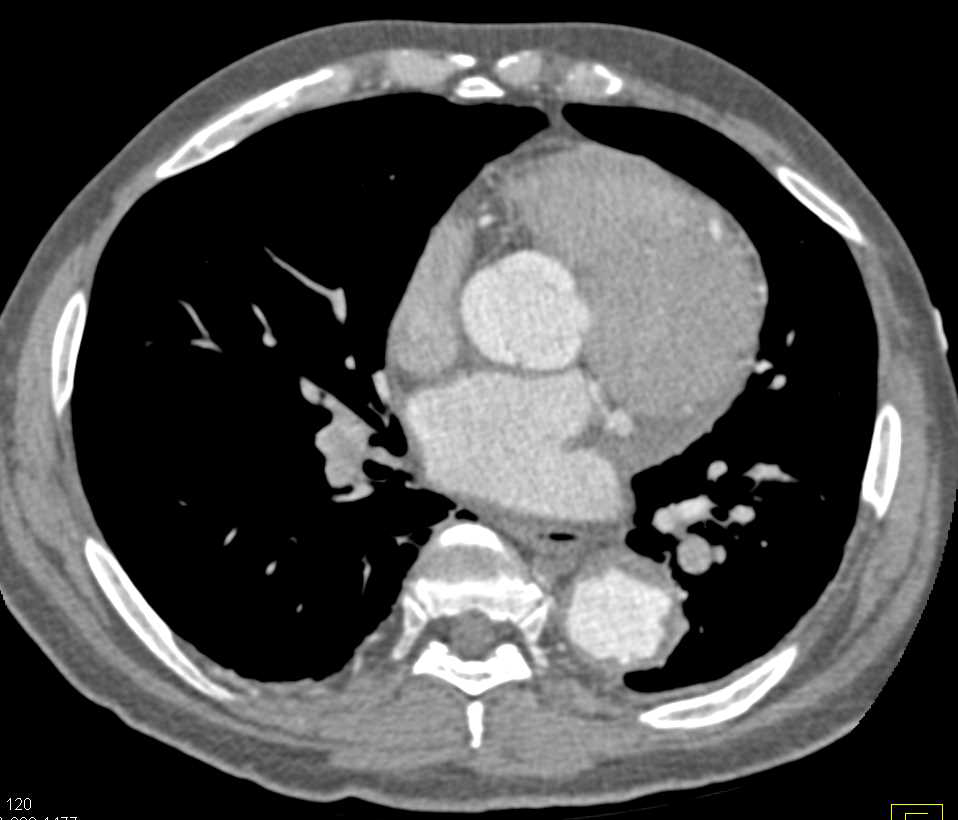

Prominent Bronchial Arteries